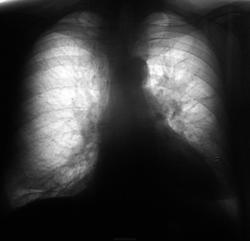

Вот флюшка, за год до "этого", когда был выявлен рак...

Зная о последующих событиях можно сказать о патологии левого корня на архивной флюорограмме.После драки мы все сильны кулаками помахать.Не ведая будущего-за норму может проскочить.

Нет, за "норму" (рентгенологических) не проскочило, но вот клиницисты... манкировали выявленное.

Центральное новообразование левого легкого, гиповентиляция верхней доли. Однако, в шестерочке что-то нечеткое затенилось.

Плеврит-то есть(междолевой).А где сама опухоль?Сомнения возникли.